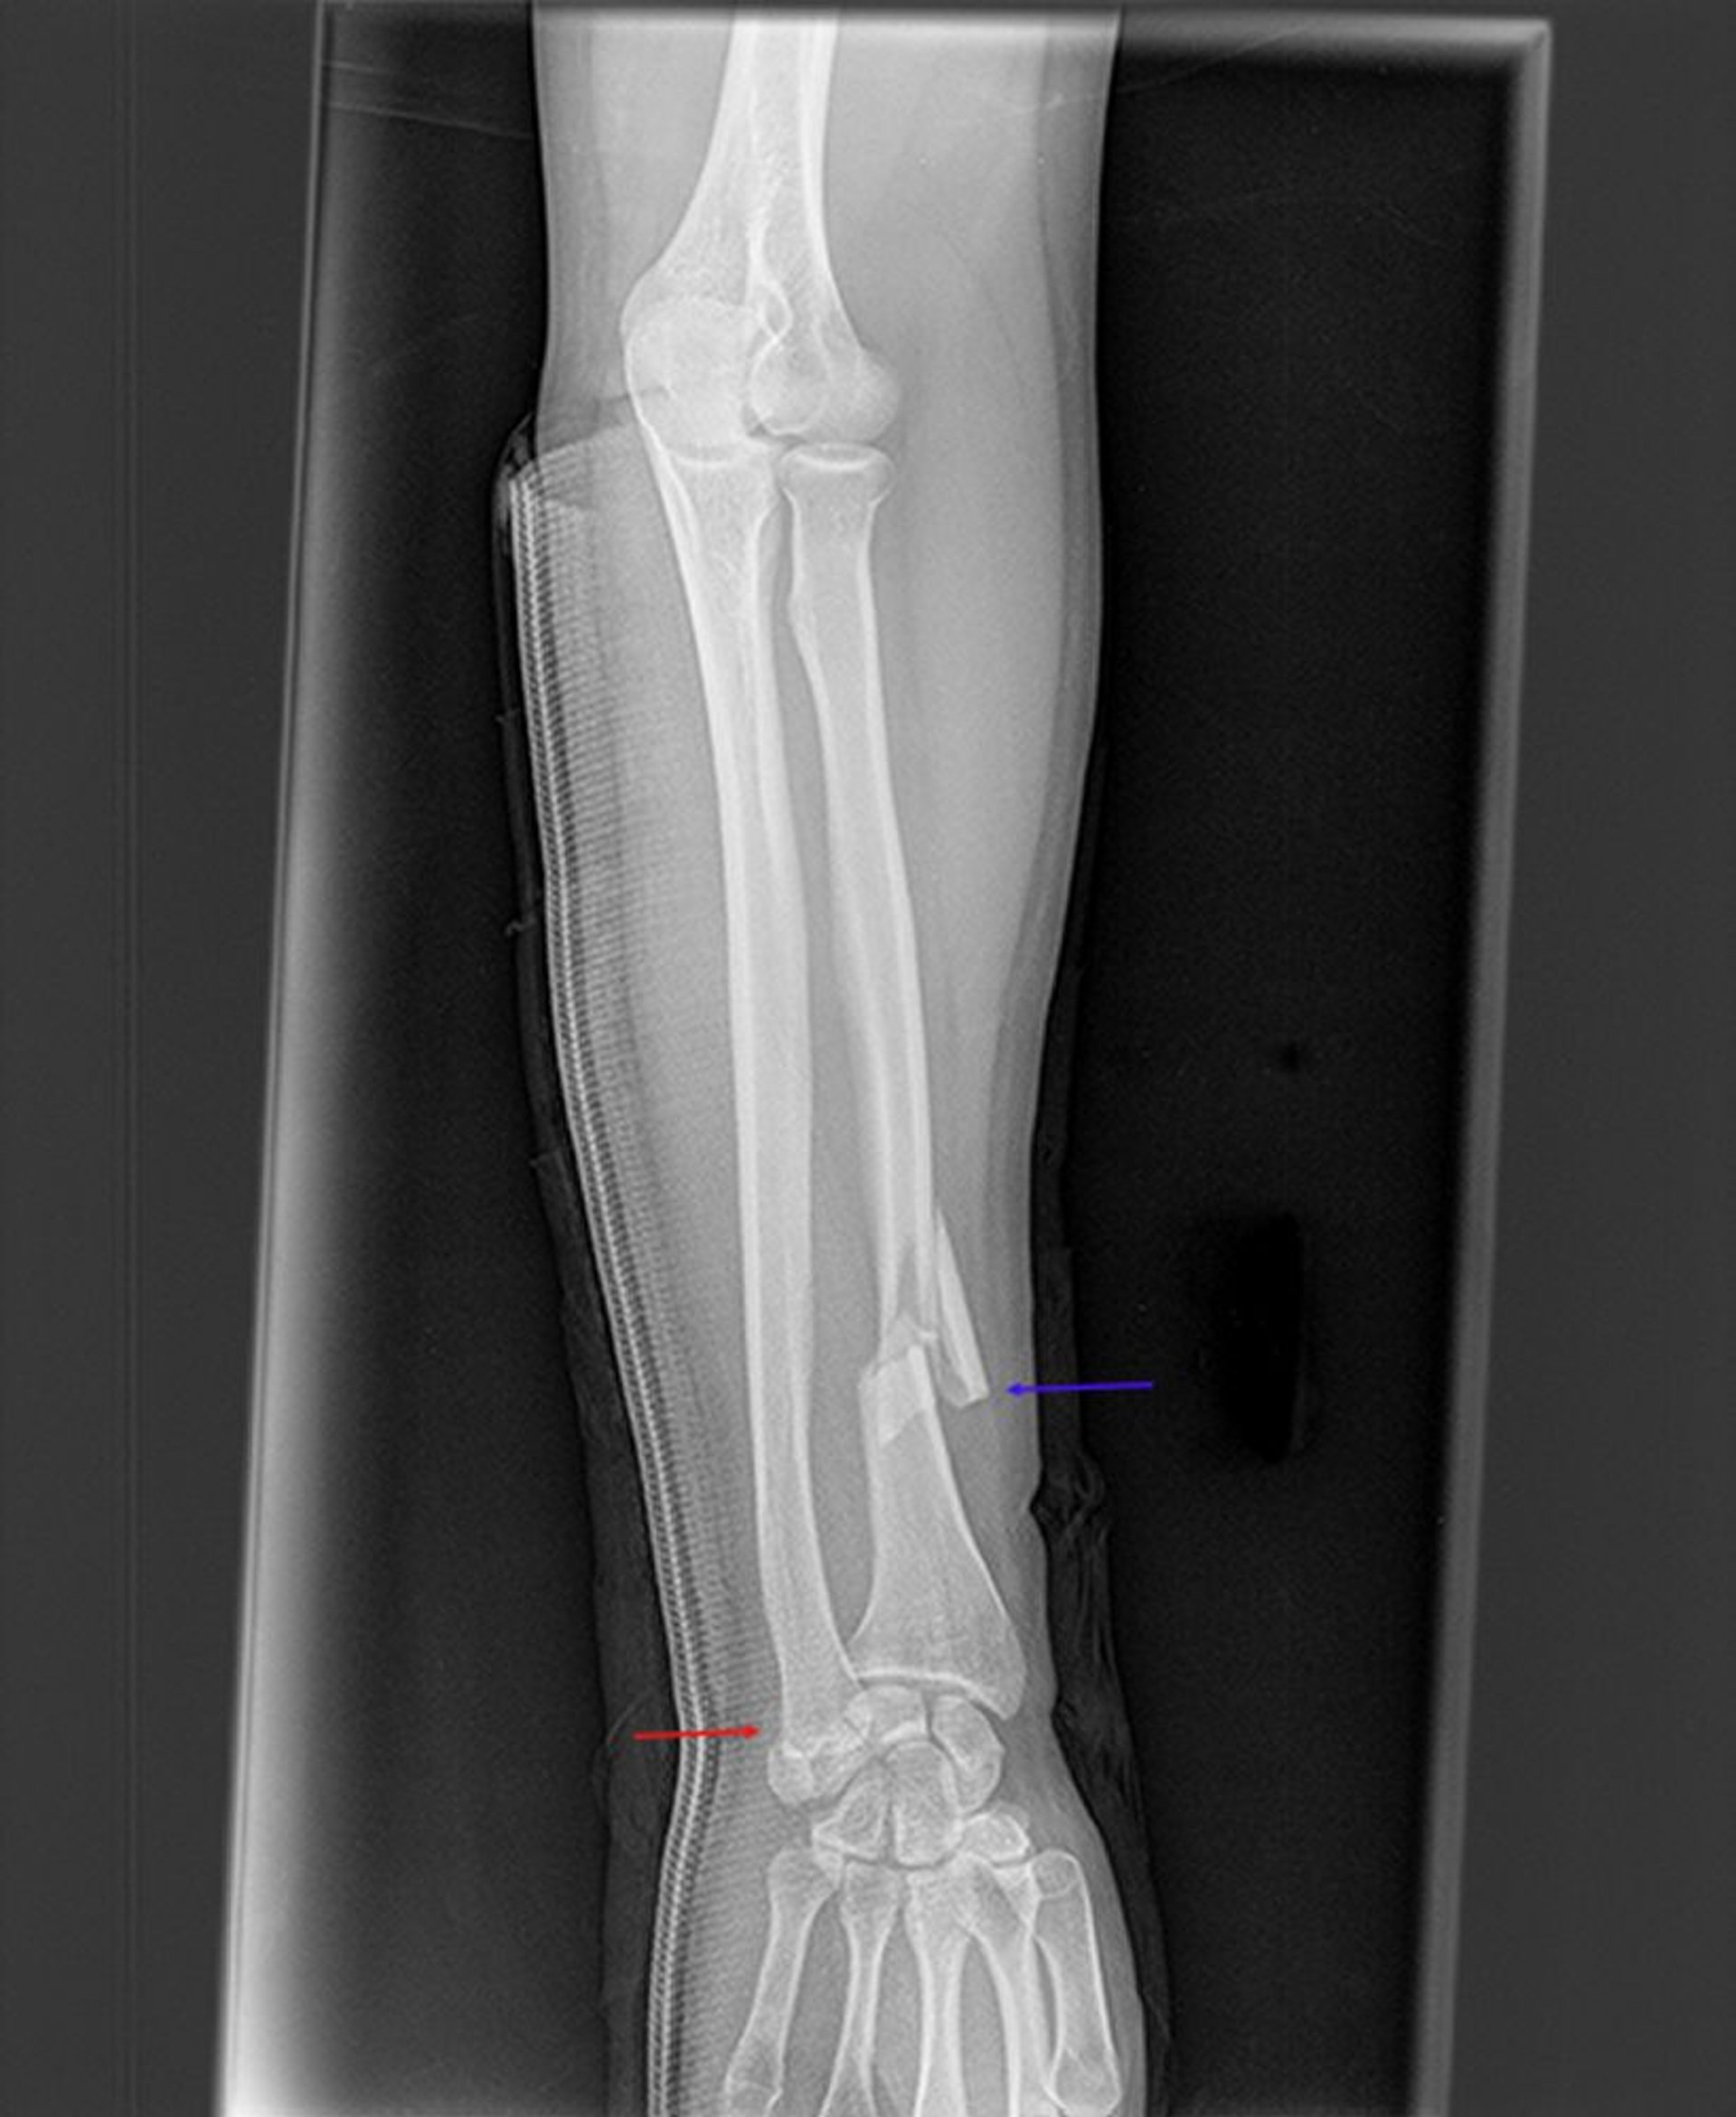

Fracture de Galeazzi

Cette radiographie montre une fracture du radius distal (flèche bleue) et une destructuration de l'articulation radioulnaire distale (flèche rouge). Les surfaces articulaires du cubitus distal et du radius distal ne sont pas alignées.

Image courtoisie de Danielle Campagne, MD.